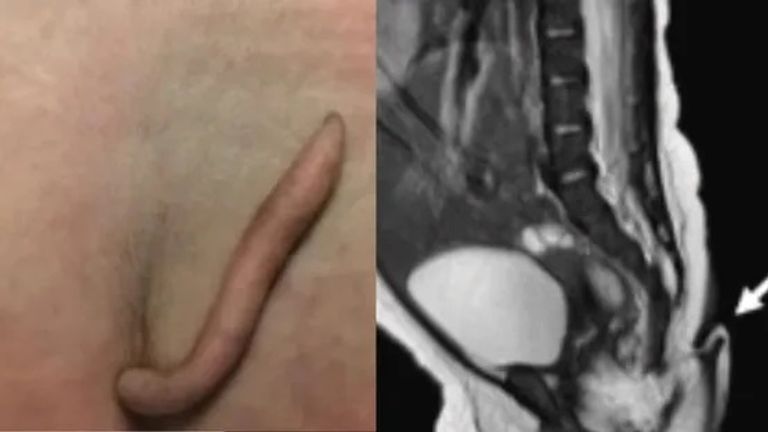

شهد مستشفى في نويفو ليون بالمكسيك، ولادة طفلة بذيل طوله 5.7 سم ناعم ومغطى بالجلد والشعر والجلد وله طرف مدبب، في حالة نادرة للغاية.

وأشار الأطباء إلى أن الذيل كان بارزا، وأسطواني الشكل ويضيق باتجاه الطرف المدبب، ويتراوح قطره بين 3 مم و5 مم، وبكت الطفلة عندما قُرِصَت بإبرة على الذيل.

وكشفت عمليات المسح أن الذيل لم يكن عاطلا عن الوظيفة وكان حقيقيا، ولم يكن نتيجة لمشكلة في العمود الفقري، وأوضح الأطباء أن الطفلة ولدت دون حدوث مضاعفات أثناء الحمل، ولم يكن لديها تاريخ سابق في التعرض للإشعاع أو التهابات أثناء الحمل، وفقا لروسيا اليوم.